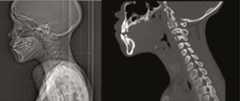

Figure 1.

Topogram and sagittal view of the neck on computerized tomography scan performed on the day of presentation showing classic “thumbprint” sign due to swelling of epiglottis.